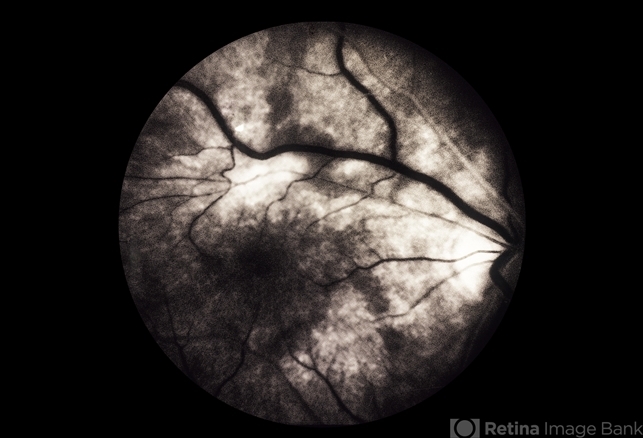

By From the Collections of Thomas M. Aaberg, MD and Thomas M. Aaberg Jr., MD

- toxoplasmosis

- FA sequence.